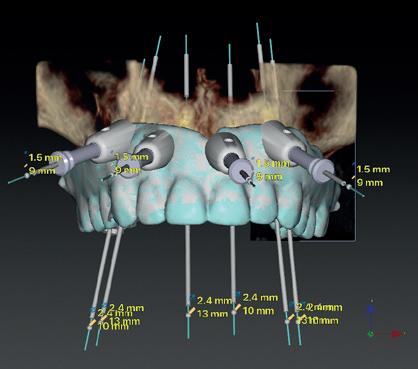

Voor het implantologisch onderzoek werd een CBCTscan (Trium CBCT, Acteon Frankrijk) vervaardigd van de edentate bovenkaak en in de software werd een planning gemaakt van 6 implantaten in de bovenkaak. De kaak kan opgedeeld worden in het front, tussen de 13 en 23 en de zijdelingse delen van de 14 t/m 17 en 24 t/m 27. Er dienen 2 implantaten in het front geplaatst te worden en 2 implantaten in de zijdelingse delen rechts en links, om een optimale verdeling van de implantaten (implant spread) te krijgen. De implantaten in deze casus werden gepland op posities 12, 22, 14, 24, 16 en 27. Tevens werd rekening gehouden met de krachtenverdeling óp de implantaten, deze zijn naar dorsaal toe forser dan in het front, daarom werd er gekozen voor brede implantaten (meer dan 5.0 mm in diameter) distaal en 4.0 mm diameter implantaten in het front. Voor de 16 was een crestale sinusbodemelevatie nodig en de 14 benodigde een kaakverbreding en verhoging.

Om de implantaten op de juiste vooraf geplande positie te implanteren, zijn er een aantal mogelijkheden (afbeelding 1 en 2). Eén daarvan is om de chirurgie guided uit te voeren, maar dat is lastig omdat de guide niet op elementen afgesteund kan worden. De guide dient dan met guide pins vastgeschroefd te worden, maar dat heeft als nadeel dat bij verplaatsing van de guide de implantaten niet op de juiste positie staan. Bij immediaat implanteren kan tegenwoordig gebruikgemaakt worden van meerdere stac-

2. Planning in de CBCT-software Acteon AIS

kable guides, die op een base guide geklikt kunnen worden. Een tweede methode is om op basis van de CBCT-scan in de mond uit te meten waar de implantaat locaties zijn en door te kijken naar referentie van de onderkaak. In deze cases werd besloten om de implantaten vrij uit de hand te plaatsen.

voor de implantaten (afbeelding 3). Hierna werd met een meetinstrument de locaties van de implantaten uitgemeten en werd een initiële osteotomie op deze locaties gemaakt. Voor de 16 werd een crestale sinusbodemelevatie met Densah boren uitgevoerd. Hierbij werd het zachte bot gecondenseerd om naar crestaal geduwd te worden, waarna het membraan van Schneider meelifte. Door de osteotomie werden 1cc botkorrels geplaatst en daarna direct het implantaat. Ter plaatse van de 14 zat een verticaal botdefect, na plaatsen van dit implantaat, werd de kaak verticaal verhoogd. Er werden 6 implantaten van het merk AnyRidge (MegaGen Implant Company, Korea) geplaatst met diameter 5.0 mm aan de distale zijdes, diameter 4.5 mm bij de premolaren en 4.0 mm implantaten bij de laterale incisieven (afbeelding 4).